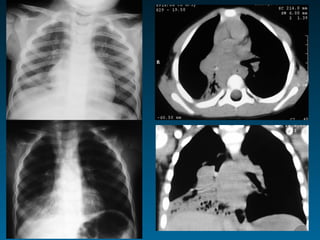

Ασυμμετρία πνευμονικής αγγείωσης

Διεύρυνση πυλών